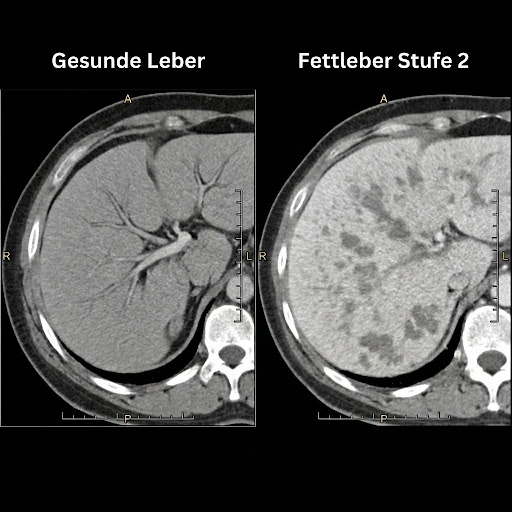

Mein Arzt meinte: „Noch kein Grund zur Sorge. Aber das müssen wir beobachten. Könnte irgendwann zu einer beginnenden Fettleber umschwenken.“

Und das heißt: Fett-Stau.

Kurz erklärt: Deine Leber muss Fette in „Transport-Pakete“ verpacken, um sie loszuwerden. Stell dir einen Paketdienst vor: Die Ware (Fett) ist da, aber ohne Kartons kann nichts verschickt werden. Dieser „Karton“ ist Cholin. Ohne Cholin bleiben die Fette in der Leber stecken. Es entsteht ein Fett-Stau. Und genau das führt zur Fettleber.

Das Verrückte: 70–90% der Menschen haben zu wenig Cholin. Und fast kein Leber-Produkt enthält es in relevanter Dosierung!